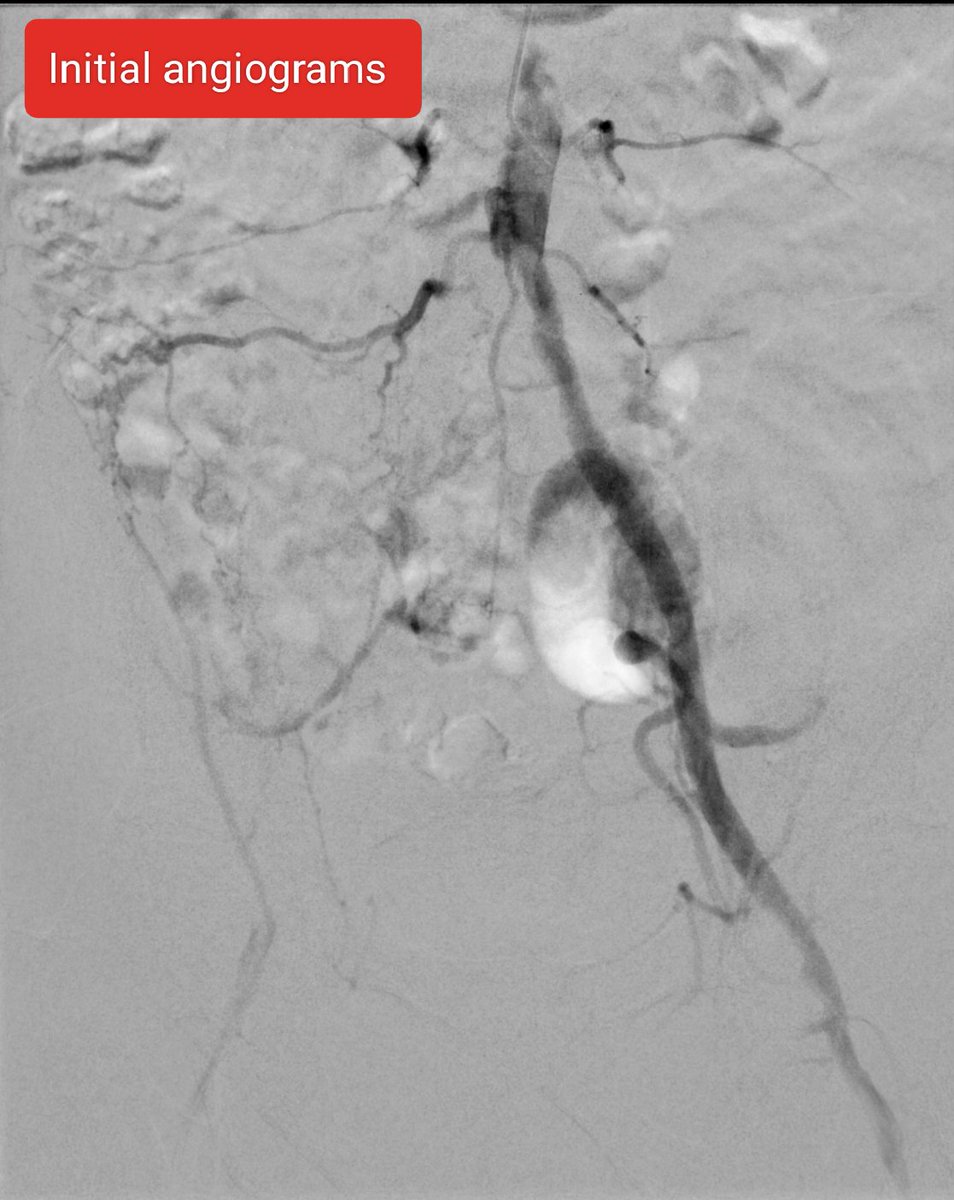

39 yo F on #OCPs. Acute Lt. LL pain n swelling, extensive #DVT, CT confirms #MayThurner #syndrome. Thrombolysis, Thrombectomy done using #AngioJet, followed by #venoplasty & stenting. #IRad is #OneStopShop! @SIRspecialists @pakIRSP @cirsesociety @rahilkassamali @drsaadrehman 1/2

Iliac occlusion crossed - felt to be acute on chronic. Angiojet pulse spray 10mg in 100ml Angiojet thrombectomy 100s Iliac thrombus cleared and underlying stenosis identified. 10mm X 8cm bare metal stent deployed. TPA infusion left for SFA and pop thrombus